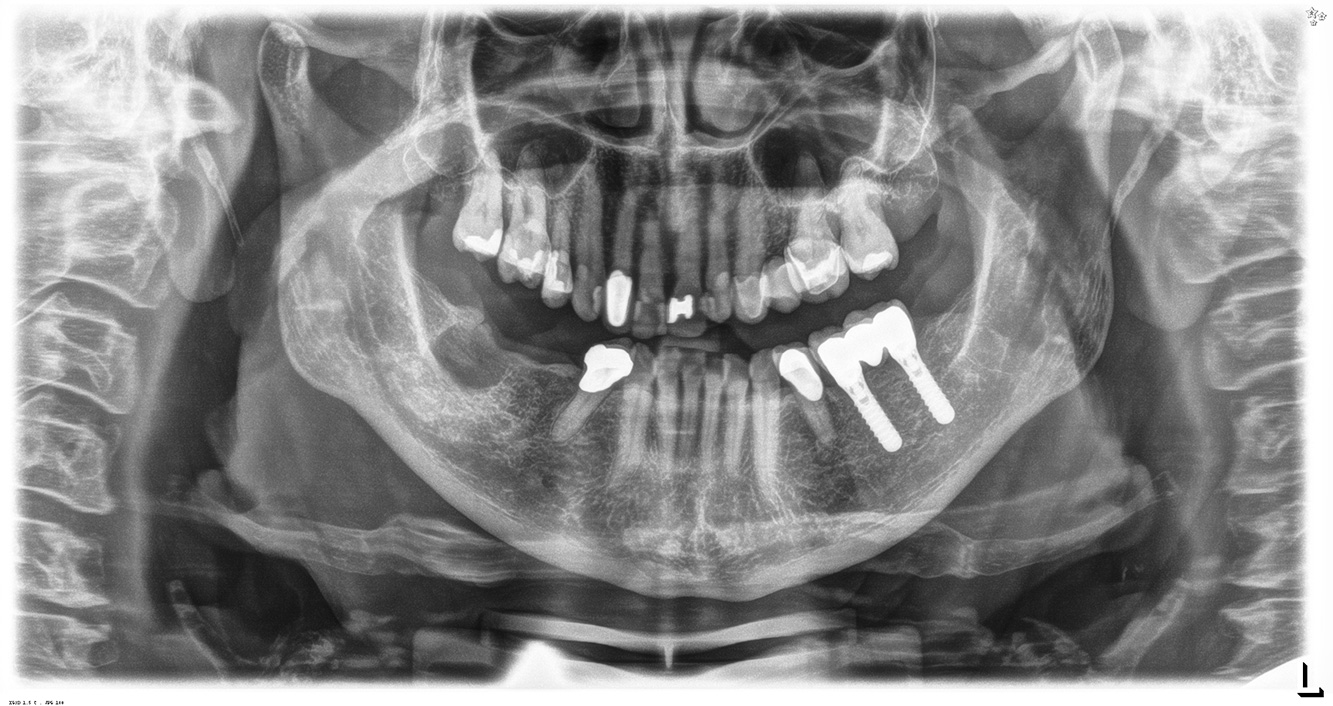

Patientenfälle nach IPCUm das Zusammenspiel der für den IPC definierten Bedarfs- und Risikofaktoren sowie die Auswirkungen einzelner Faktoren zu illustrieren, dienen nachstehende Fallbeispiele*. Die mundgesunde DiabetikerinEine 51-jährige mundgesunde Diabetikerin stellt sich zur Präventionssitzung vor. Die Blutzuckerwerte sind stabil bei einem HbA1c = 6,2%, folglich gilt sie mit dem entsprechenden Medikament Metformin (Antidiabetikum) als suffizient eingestellt. Die Patientin hat keine bestehenden Versorgungen oder orale Vorerkrankungen. Anhand der aktuellen Befunde lässt sich eine Gingivitis bei sonst stabilem parodontalem Zustand (Stage II, Grad B) feststellen. mehr Infos Fallpräsentation: Management komplexer ZahnprothetikEs ist längst bekannt, dass Mundgesundheit und Allgemeingesundheit in direktem Zusammenhang stehen und einen zum Teil bidirektionalen Einfluss aufeinander haben. Die Berücksichtigung beider Faktoren sind bei der Planung der oralen Prävention und Therapie der Patienten in der Zahnarztpraxis unabdingbar. Dabei ist oberstes Ziel, die Gesundheit und die Lebensqualität der Patienten sowohl aus zahnmedizinischer -und medizinischer Sicht zu erhalten. mehr Infos Der (mund)-gesunde Patient mit ImplantatenDer 55-jährige Patient gibt in der Anamnese an, keine Allgemeinerkrankungen zu haben und keine Medikamente einzunehmen. Die Lebensgewohnheiten des Patienten sind ebenfalls unauffällig. Der Patient hat einige zahnärztliche Restaurationen und zwei Implantate (2. und 4. Quadrant). Anhand der aktuellen Befunde lässt sich eine Gingivitis bei stabilem parodontalen Zustand am reduzierten Parodont (Stadium III, Grad A) feststellen. mehr Infos Der gesunde Patient mit parodontaler Vorerkrankung & PeriimplantitisEin 52-jähriger Patient stellt sich zur Präventionssitzung vor. Der Patient hat keine Allgemeinerkrankungen und nimmt keine Medikamente ein. Er hat verschiedene zahnärztliche Versorgungen und zudem zwei aktive kariöse Läsionen. Außerdem verfügt der Patient über vier Implantate (2., 3. und 4. Quadrant). Es zeigt sich eine parodontale Vorerkrankung (Stadium IV, Grad B). Derzeit herrschen stabile parodontale Verhältnisse, lediglich am Implantat regio 36 zeigen sich Sondierungstiefen (ST) von 5 mm. Zudem lässt sich eine Gingivitis feststellen. mehr Infos Der Diabetiker mit ParodontitisDieser Fallbericht eines 52-jährigen Mannes mit Typ-2-Diabetes und Parodontitis hebt hervor, wie durch individuelle Vorsorgemaßnahmen, die Gesundheit des Zahnhalteapparates erhalten bzw. das Fortschreiten der Erkrankung kontrolliert werden kann. mehr Infos Der 28-jährige Raucher mit ZahnerosionenDieser Fallbericht eines 28-jährigen Rauchers mit Zahnerosionen zeigt die Bedeutung personalisierter Patientenprofile. Er unterstreicht die Notwendigkeit, sowohl die Mundgesundheit als auch die allgemeine Gesundheit zu berücksichtigen, um Erkrankungen der Zähne bzw. des Zahnhalteapparates effektiv zu verhindern. mehr Infos Der Endokarditis-Patient mit aktiven KariesläsionenDer Patient ist 39 Jahre mit Z.n. Herzklappenersatz wegen Klappenfehlers und Endokarditis. Als Antikoagulans (Gerinnungshemmer) wird regelmäßig ASS 100 eingenommen. Aus dem Bereich Lebensstil ist die Ernährungsweise als kariesfördernd einzustufen, da mit hoher Regelmäßigkeit zuckerhaltige Lebensmittel sowie sechs bis sieben Mahlzeiten täglich verzehrt werden. Die Mundgesundheit des Patienten zeigt ein mittleres Kariesrisiko mit aktiven Läsionen. Das Parodontitisrisiko ist niedrig, es besteht eine Gingivitis. Es ergeben sich folgende Empfehlungen für die Prophylaxebehandlung. mehr Infos Die gesunde Patientin mit parodontaler VorerkrankungDie 68-jährige Patientin hat keine zahnmedizinisch relevanten allgemeingesundheitlichen Vorerkrankungen oder Medikation, auch aus dem Lebensstil ergibt sich kein besonderes Risiko. Die Patientin hat zwei Implantate (3. Quadrant, seit fünf Jahren) sowie eine parodontale Vorerkrankung (Parodontitis Stadium IV, Grad B) mit Zahnverlust. Derzeit zeigen sich stabile parodontale Verhältnisse. Für die Prophylaxesitzung ergeben sich vier Empfehlungen in den Bereichen Anamnese/Befund, Motivation/Instruktion, der Wahl der geeigneten Instrumente und für Resümee/Folgetermin. mehr Infos